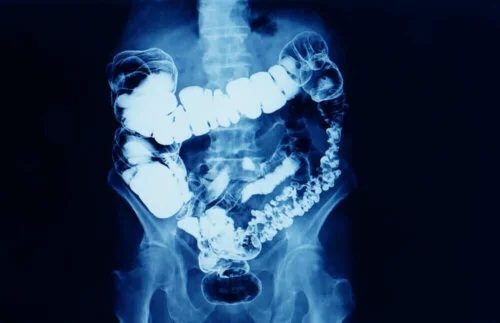

Glicerolul este ingredientul activ al supozitoarelor cu glicerină. Este o substanță care își exercită acțiunea laxativă atunci când este administrată rectal. Acest efect apare deoarece, în urma administrării de supozitoare, scaunul se înmoaie. Se produce un efect de iritare ușoară la nivel local, stimulându-se peristaltismul intestinal.

- Efect iritant local asupra mucoasei rectale: Efectul iritant nu afectează pereții intestinali. Provoacă contracția rectului, favorizând expulzarea scaunului.

- Efect osmotic: Glicerolul absoarbe apa. Aceasta, împreună cu proprietățile lubrifiante ale glicerolului, înmoaie scaunul și facilitează eliminarea acestuia.